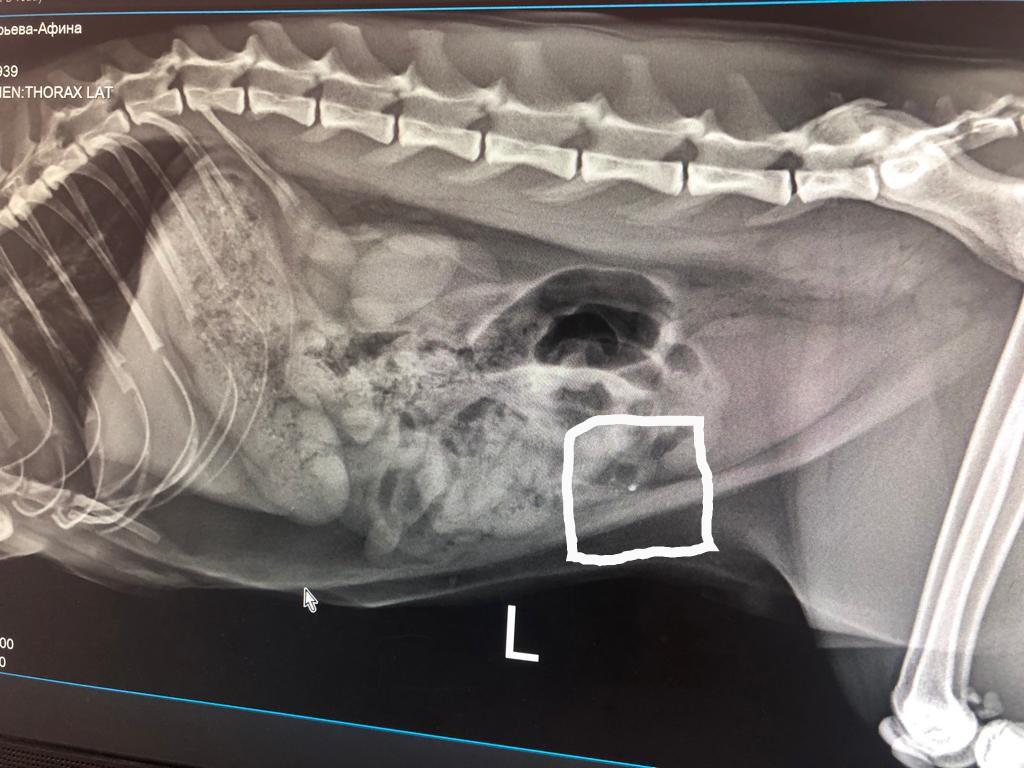

Рентгенологическая диагностика саркомы у кошек

Раздел: Визуальный дайджест